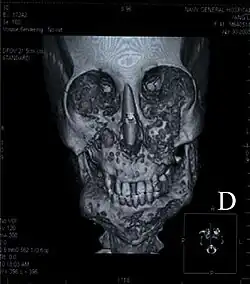

| Three-dimensional computed tomograph of a 41-year-old woman diagnosed with cherubism shows a remarkable expansion of the mandible, which can lead to a soap bubble appearance, and the bilateral bulges of the maxilla | |